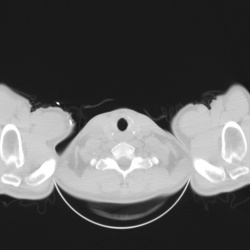

Девочка 2007 г/р отправлена ЛОР врачом на КТ височных костей с диагнозом тугоухость. Жалобы на снижение слуха слева с августа. Коллеги очень важно ваше мнение по поводу изменений в среднем ухе...